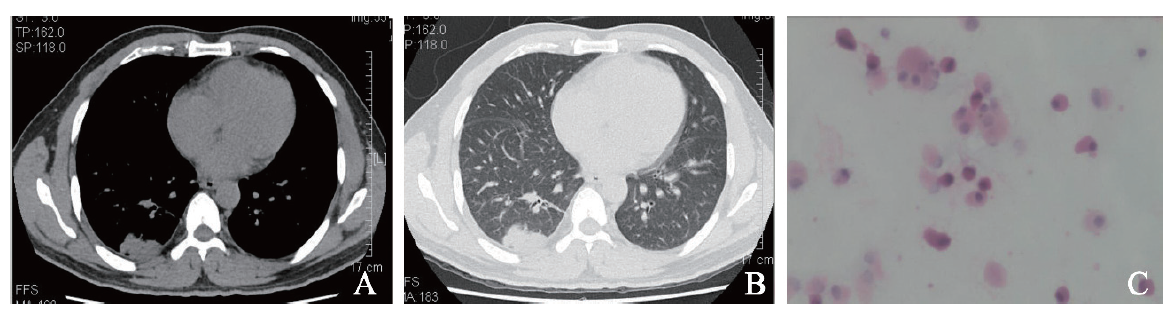

例2 患者男,68岁。因左肺腺癌1年返院复查于2017年7月18日收入我科。1年前患者因后背痛10月余,加重伴胸痛20 d在我科经胸部CT、肿瘤标志物、胸腔积液病理及免疫组化等检查确诊为左肺腺癌,于2016年8至12月行多西他赛120 mg、洛铂50 mg方案化学治疗6个疗程,过程顺利。既往吸烟30年,每日1包,戒烟2年,余无特殊。入院体格检查:体温36.7 ℃,脉搏100次/分,呼吸20次/分,血压144/93 mm Hg。双肺呼吸粗,未闻及干、湿性啰音。血常规示血红蛋白119 g/L,白细胞7.98×109/L,血小板 155×109/L。癌胚抗原21.0 μg/L,神经元特异性烯醇化酶、细胞角蛋白19片段、鳞状细胞癌相关抗原测定等正常。复查胸部螺旋CT平扫+增强扫描示左侧肺癌较前增大,左肺、左侧胸膜多发转移瘤较前稍增大(图2A、B)。遂完善BAL检查。7月25日BAL的HE涂片及液基细胞学检查示较多泡沫样细胞及少量上皮细胞,未见确切癌细胞(图2C)。予培美曲塞800 mg、顺铂120 mg化学治疗,过程顺利,予出院。随访至2018年8月5日,患者再次化学治疗,过程顺利。

图2 例2肺腺癌患者的胸部CT及BAL涂片结果

A:胸部CT纵隔窗;B:胸部CT肺窗;C:BAL涂片(HE染色,×400)